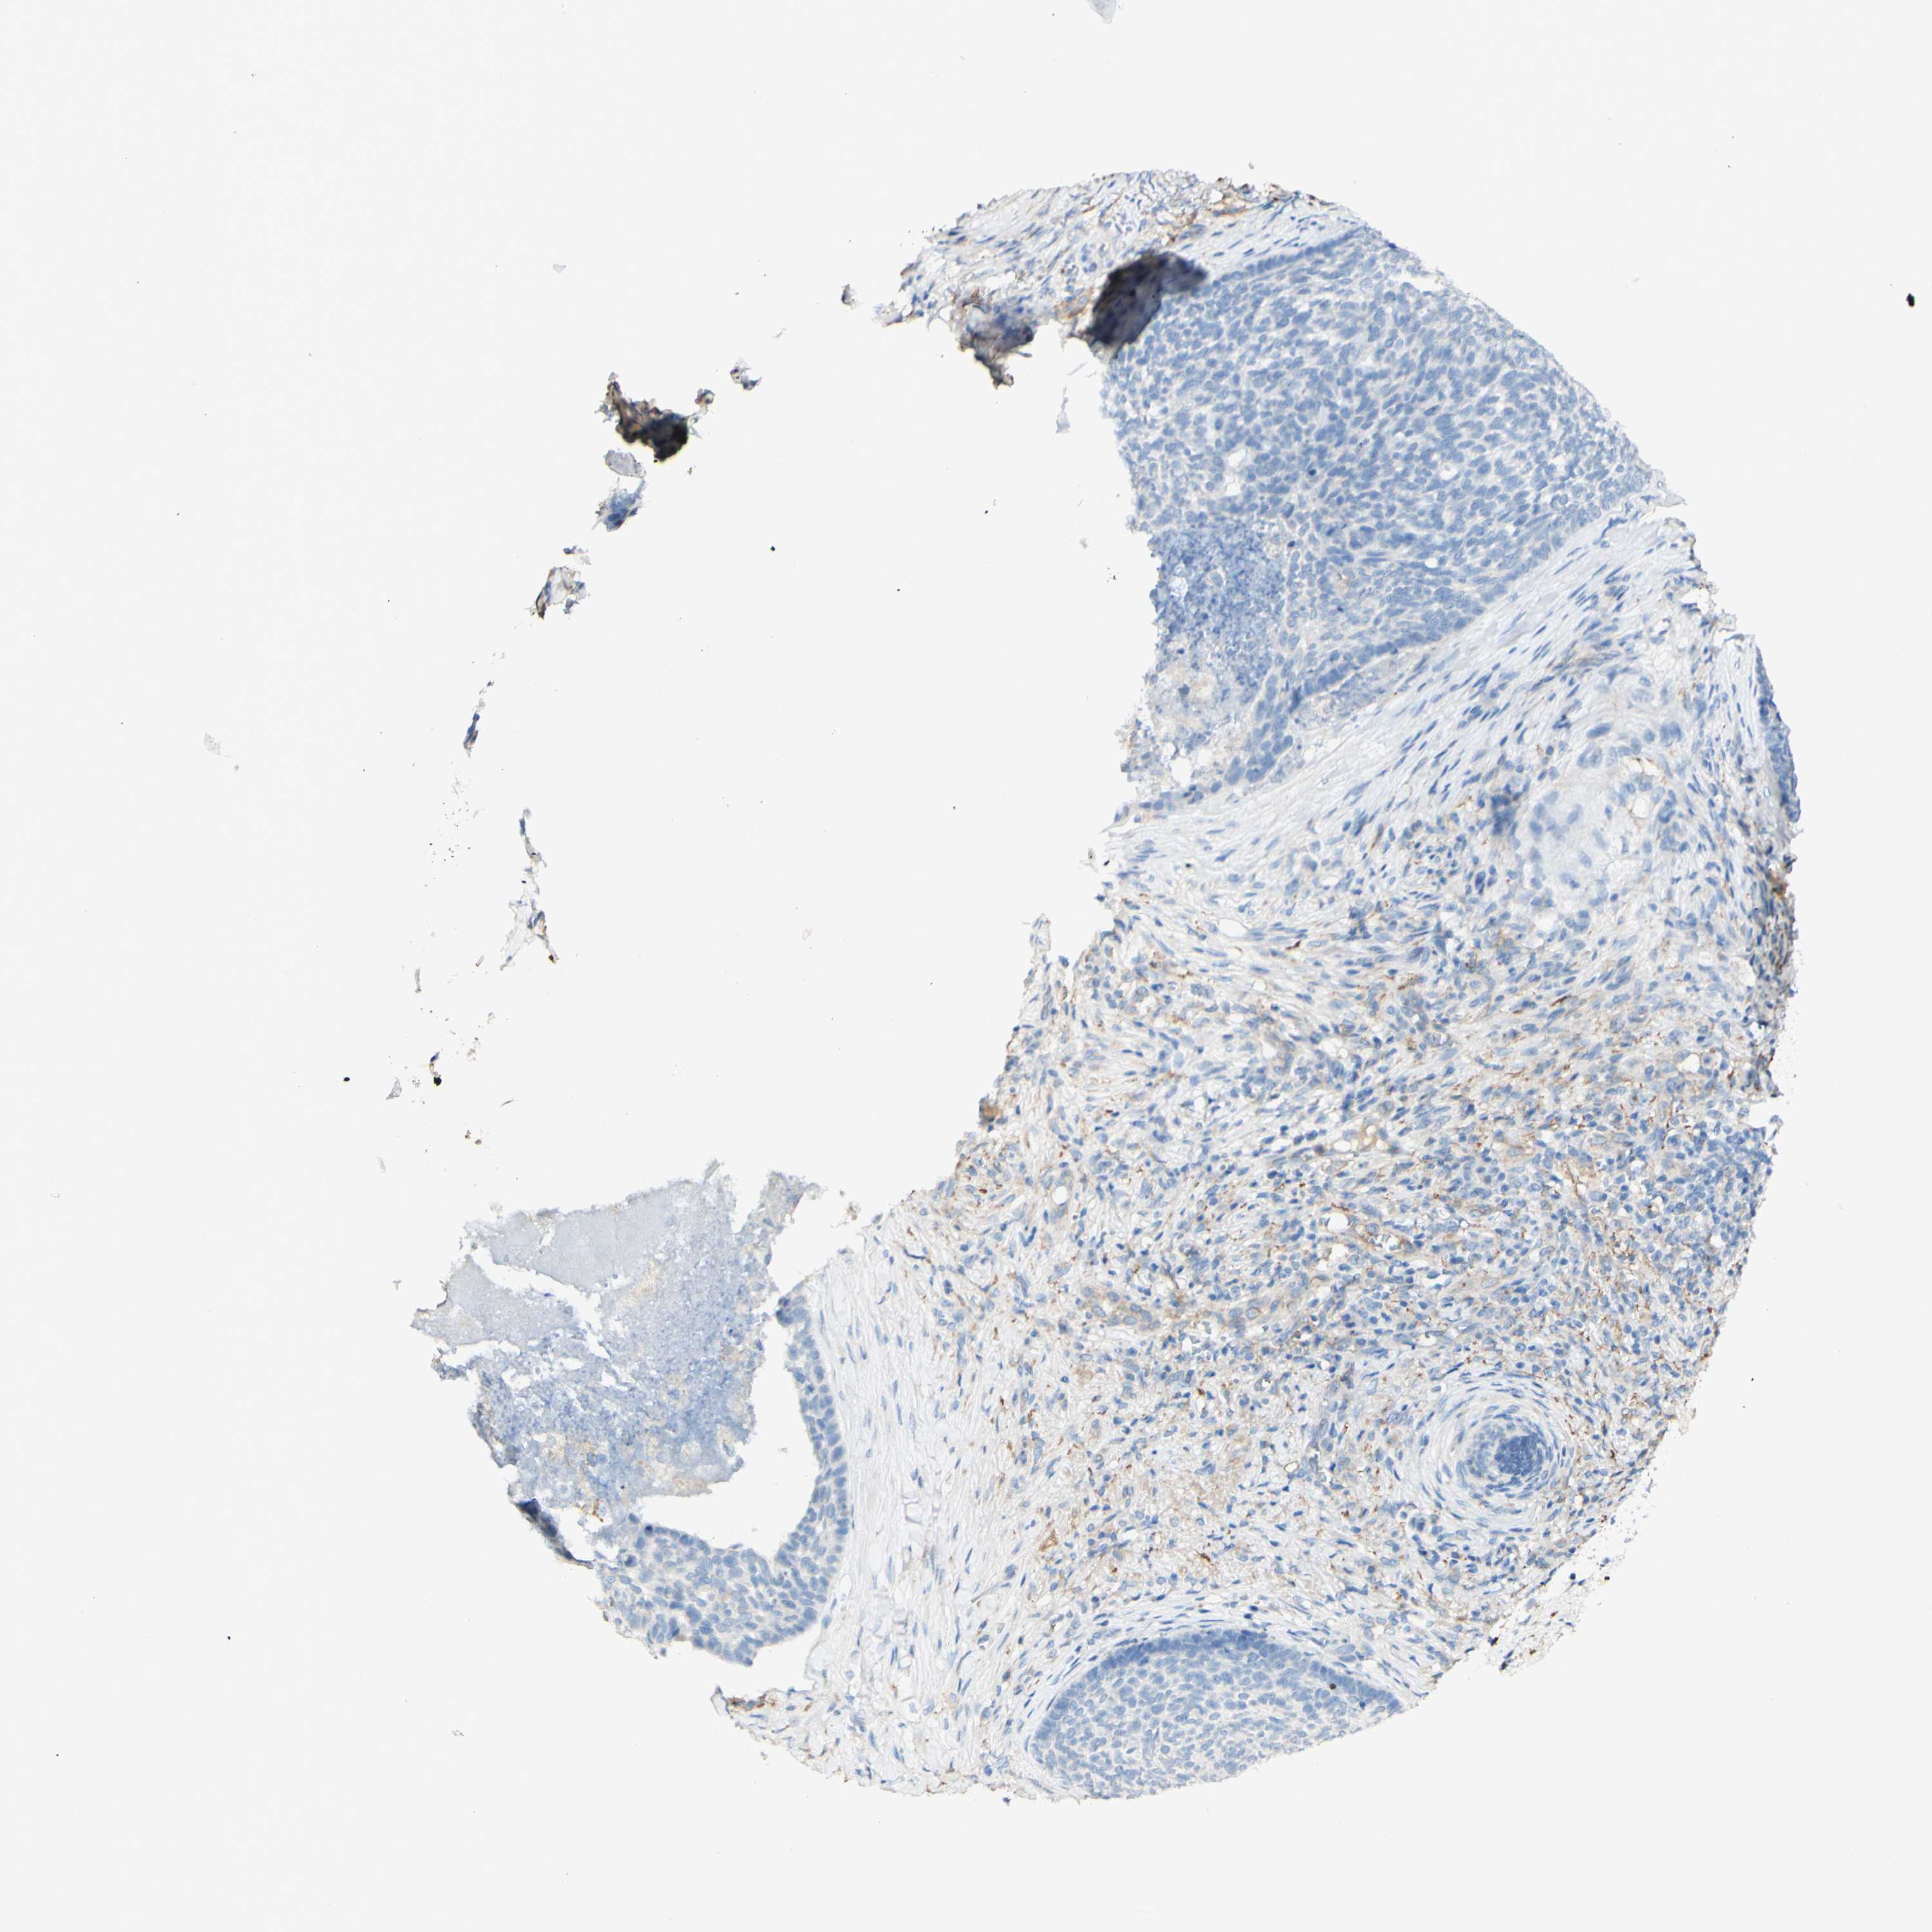

CANCER SKIN CANCER Show tissue menu

SKIN CANCER - Protein expressioni

A mouse-over function shows sample information and annotation data. Click on an image to view it in a full screen mode. Samples can be filtered based on level of antibody staining by selecting one or several of the following categories: high, medium, low and not detected. The assay and annotation is described here.

Each image is clickable and will lead to virtual microscopy that enables deeper exploration of all samples and also displays staining intensity scores, fraction scores and subcellular localization as well as patient and tissue information for each sample.

Antibody HPA012122

Squamous cell carcinoma, NOS

Basal cell carcinoma

Adnexal tumor, benign